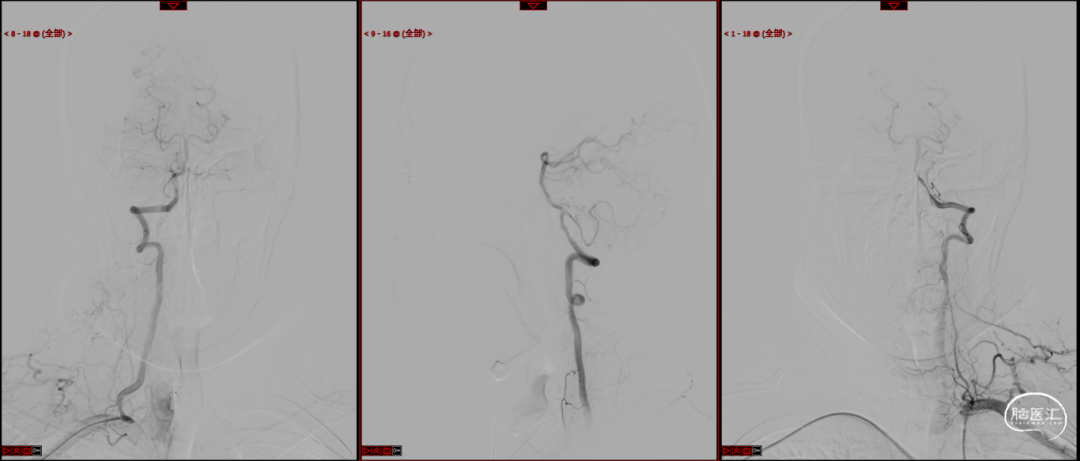

载瘤动脉远端血管直径:2.4mm

载瘤动脉近端血管直径:2.5mm

动脉瘤尺寸:(瘤颈口宽度2.0mm/瘤体高度1.86mm/瘤囊宽度1.85mm)

密网支架:强易达Choydar血流导向装置 FD250-15

微导管:畅医达accessway 17系统

微导管到位:Synchro微导丝引领支架微导管通过病变血管进入大脑中动脉M2段。

支架到位,原位释放,前段打开。

造影确认支架远端打开充分,贴壁良好,继续推送支架。

支架全部释放,调整张力,微导管通过支架,回收输送导丝。

支架内使用成襻微导丝进行按摩,使支架充分贴壁。

术后造影:支架充分覆盖动脉瘤瘤颈,贴壁良好,瘤体内可见造影剂滞留。

术后支架显影:定位精准,未覆盖颞前动脉及大脑前动脉。